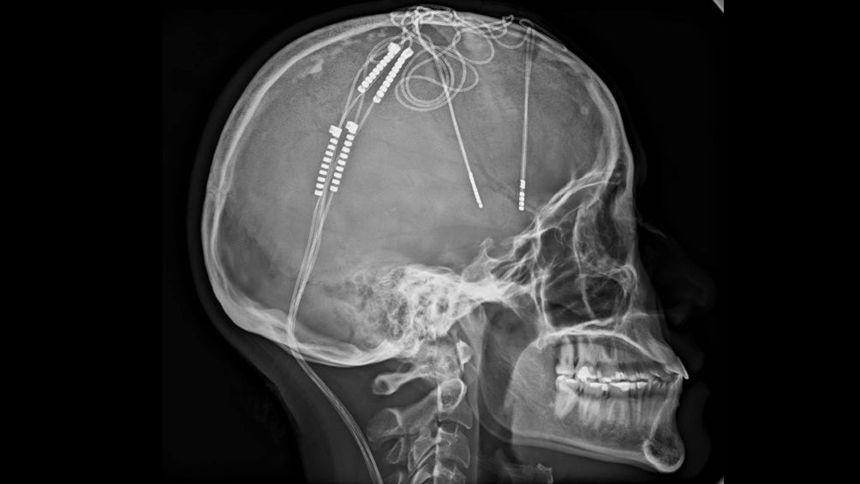

“Estuve seis horas despierta durante la cirugía. Superó toda la ficción. Sentía que mi mente estaba siendo reprogramada”, expuso. La operación, encabezada por el neurocirujano William Contreras, implicó la implantación de electrodos en su cerebro y una batería en el pecho que emite impulsos eléctricos para modular la actividad cerebral.